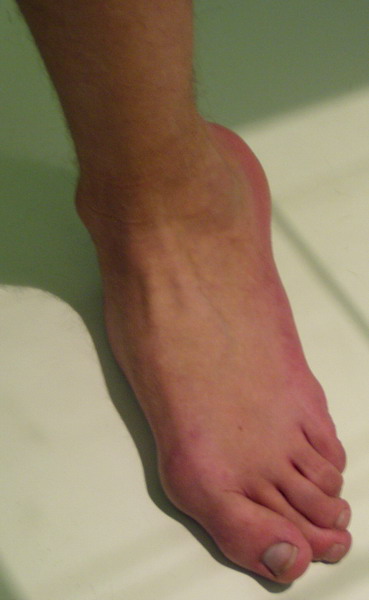

Пациент 15 л., болезнь Литтля, спастический нижний парапарез, интеллект высокий. Ребенок настроен на активный образ жизни. С недавнего времени начал ходить без дополнительной опоры. Появилась проблема с левой стопой - во время ходьбы опора приходится на смещенную кнутри таранную кость.

Может образоваться болезненный натоптыш или язва. Общепринятой операцией является трехсуставной артроде с мобилизацией таранной кости. Выполнять такую операцию у спастика и в раннем возрасте проблематично. Родстьвенники тем более готовы материально и морально осуществить хирургическое лечение за рубежом, если оно показано и возможно. Предпочтительно в Австрии и Германии. Если кто-то посоветует координаты таких клиник - были бы признательны.